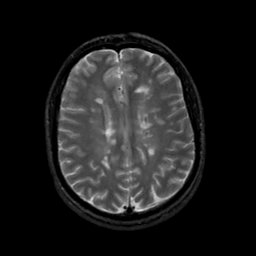

MR Study #19, August 25, 1991 -- Slice #33

[Home][Help][Clinical][Tour 1][Tour 2] Slice 33